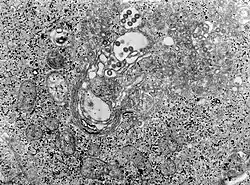

![]() micrografía MET de tejido infectado con el virus de la fiebre del valle del Rift | ||